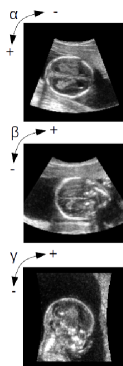

4.5 Regional performance

The regional performance of the network is shown as a map of false-positives and false-negatives for different gestational ages in Fig. 6. It can be observed that overall the network is very consistent throughout all regions of the brain with the exception of the brain stem. This is most likely due to this structural information not being visible in the US scan. There is, however, one region of the brain that has worse regional performance for later gestational weeks: the space between the occipital cortex and the cerebellum. This is likely due to the fact that the annotations are based on the brain tissue and do not include the cerebrospinal fluid. As the brain develops, the separation between occipital cortex and cerebellum becomes more pronounced. However, since the US does not offer a good contrast between the tissue and the cerebrospinal fluid, this separation is not visible and therefore appears as a false positive.